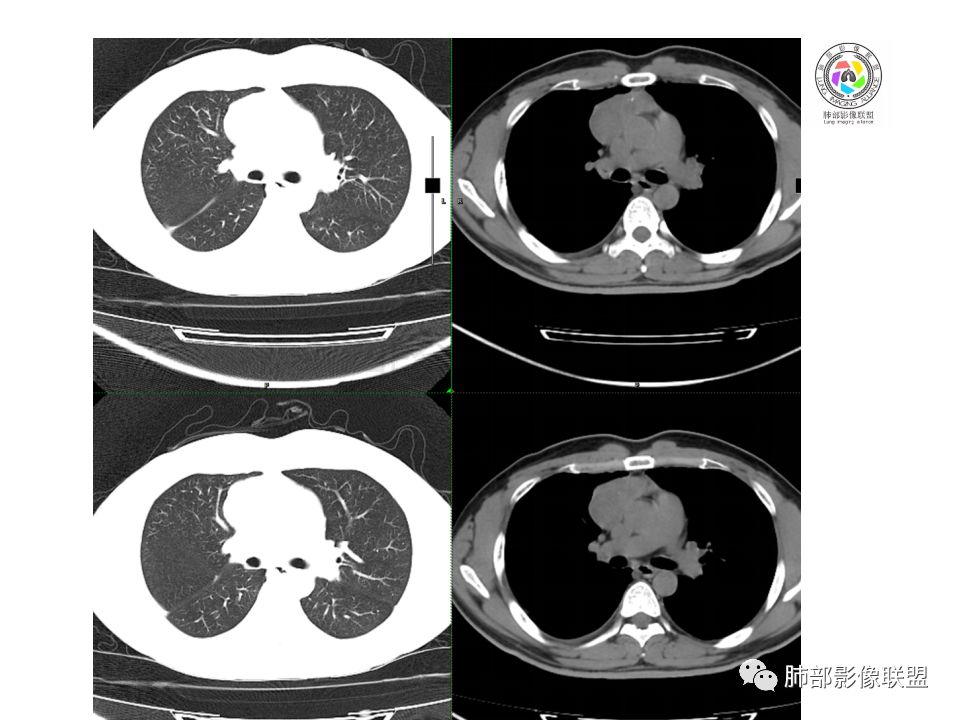

晨读:前纵隔占位,密度不均,沿着右侧纵膈延伸到肺门水平,周围支气管推移,大血管向内推移。临床有重症肌无力,考虑胸腺瘤可能,鉴别淋巴瘤。

右前纵膈肿块,偏一侧生长,形态欠规则,密度不均匀,其内可见小点状钙化,双肺多发小叶中心结节及钙化灶,右侧胸膜增厚(有陈旧性结核可能),青年男性(27岁),没有增强,考虑,1,前纵隔生殖细胞瘤2,精源细胞瘤

右前上纵隔占位,瘤肺交界面清楚,提示纵隔来源,其内有点状钙化,右侧胸腔积液,有临床症状,年龄轻,考虑生殖来源可能,胸腺瘤待排,请结合临床相关检查或CT增强进一步检查。

前纵隔占位,伴点状钙化;上腔静脉后移位。伴右胸膜局限性增厚,临床有重症肌无力,病人年轻,考虑胸腺瘤可能,鉴别生殖源性肿瘤。

右前纵隔占位,有分隔`低密度、点状钙化,边缘光滑,侵袭心包不明确,伴右胸少量积水,考虑恶性,生殖源性可能大,有视物不清,是否脑转移待查。建议HCG丶AFP检查。鉴别1:胸腺瘤、癌,30一40岁以下,少见,但有眼脸下垂,肌无力,待排除。2:淋巴瘤:侵袭性不强,有点状钙化,不支持。3:畸胎瘤:有低密度丶钙化,建议增强进一步明确。4:神经源性:一般后纵隔常见,不支持。5:LCD:症状少见,可以有树枝状钙化,浆细胞型可以有低密度,增强进一步明确

没有增强,好像两个病灶,上方三角形的像是胸腺增生。下方肿块,没有增强显得更难了,微钙化,轻度分叶,像有坏死低密度影,右侧少量胸水,胸膜受侵.,有视物模糊眼睑下垂。考虑胸腺瘤B1型及以上、B2型可能或生殖细胞瘤

前纵隔右区占位性病变,上区与胸腺延续,下区呈分叶状,尽管年龄<30还是首先考虑胸腺瘤,侵袭性可能性大(眼睑下垂不知是否有关)。鉴别主要是生殖细胞类肿瘤,主要是精原细胞瘤。另左肺上叶结核球,右侧胸腔积液,需除外结核性胸膜炎和转移

右前纵隔肿块,边界清楚,密度欠均匀,内似有分隔和低密度区,似有多结节融合,几乎从上到下,年龄较轻,不是胸腺瘤好发年龄,但却有视物模糊,眼睑下垂症状,考虑淋巴瘤?鉴别胸腺瘤?结核?

右前上纵膈肿块,内有点状钙化和少许小片状坏死,局部边界似欠清,右侧胸膜腔少量积液,年轻男性,小于30岁,有重症肌无力,虽然年龄偏轻,仍先考虑胸腺瘤,代排生殖源性肿瘤

晨读前纵隔肿块,偏右侧,密度不均,见点状钙化灶及分隔状低密度影。胸腺瘤>生殖细胞瘤>淋巴瘤

前中纵隔(胸腺癌区)不规则肿块,密度不均,有坏死区、点状钙化,边缘不会整肿块偏向右侧,向心包流注感,右胸腔少量积水。患者27岁,重症肌无力表现。